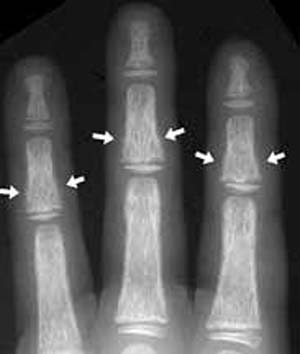

avenjers71 (7) گزارش تخلف پوکی استخوان یا استئوپروز پوكی استخوان عبارت است از كاهش توده (دانسیته) استخوانهای بدن و شكننده شدن بیشتر از معمول انها است.با افزایش سن مخصوصا در خانمها احتمال ایجاد استئوپروز بیشتر می شود. در سن ۵۰ سالگی به بعد بافت استخوانی و مواد معدنی ان در خانمها به سرعت كم شده بطوریكه بیشتر خانمهای ۷۰ ساله دچار درجاتی از پوكی استخوان هستند.اهمیت استئوپروز در احتمال ش... 8 0 0 51 5 سال پیش